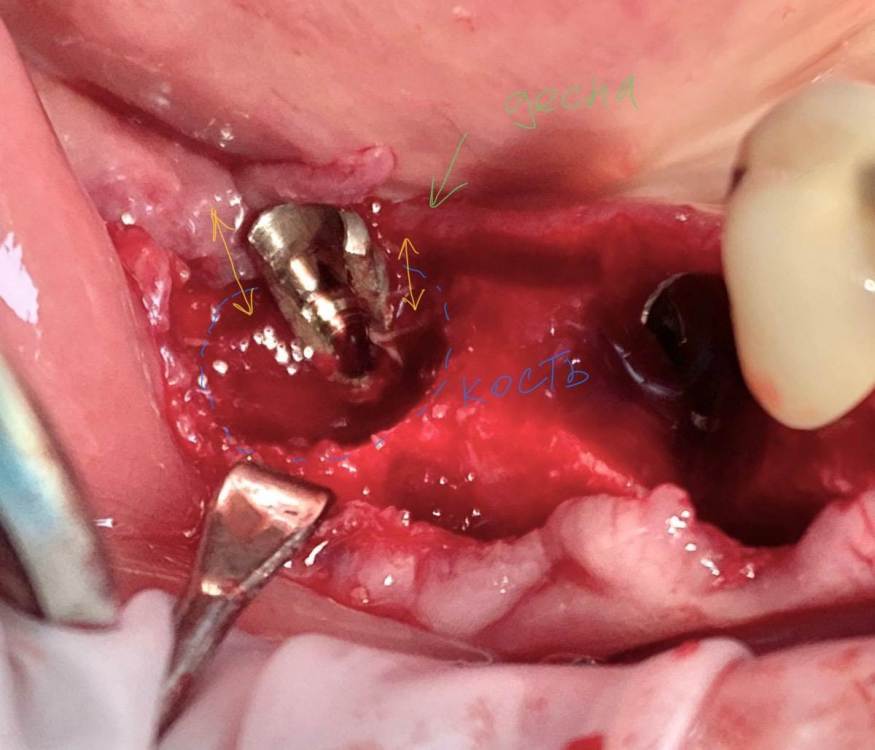

колесников Опубликовано 6 июля, 2022 Поделиться Опубликовано 6 июля, 2022 Здравствуйте коллеги! Впервые вижу перелом Астры. Впервые получил перелом «своей»Астры. Вероятно ещё никто не видел перелом Астры профайл. Диаметры 4.5 и 5.0. Самое неприятное что это произошло за 1,5 года. Ошибка протезирования. Перегруз. Резорбция. Фрактура. Из интересного. Одновременно с имплантацией была произведена контурная пластика поднадкостнично,графт шурос. Это работает. Ставим галочки и двигаемся дальше. 2 1 1 Ссылка на комментарий

колесников Опубликовано 6 июля, 2022 Автор Поделиться Опубликовано 6 июля, 2022 5 часов назад, Aquarius сказал: Спасибо за столь познавательный кейс!!! Я где- то читал, что вроде как перегруза на полностью интегрированных имплантах быть не может. Вроде как первично надо высвободить какую-то площадь импланта от кости ( воспаление, резорбция) чтобы он треснул. А не наоборот. Автор сего высказывания ссылался на то, что в связке имплант-коронка есть куда более слабые места , чем стенка интегрированного импланта. Например, фиксирующий винт. Для конического соединения это утверждение не применимо. Очень часто получаем холодную сварку имплант-абатмент,винт совершенно не работает. Протокол отработан как автомат Калашникова,платформа относительно Зенита и вершины гребня,высота уступа,наличие и ширина прикреплённой слизистой. Далее процесс запускается вспять и через два года наблюдаем прирост кости на скосе гребня. Радиальная Резорбция в виде кратера это всегда перегруз. Импланты не болят. Вокруг них нет посредника-связки,нет проприорецепции. Между тем диссонанс окклюзии со временем нарастает,тк зачастую имеются разнородные по плотности материалы в полости рта. Отчасти пациент тут виноват,не продолжил лечение,пропал на год. Но основная вина ортопеда. Причина личная. Коронка на 45 осталась от старого моста,44 вовсе пародонтитный. Желая их «спасти» вывел из прикуса,основная нагрузка справа упала на импланты. Третий сектор провисший мост 34.35-38 с подвижными 34,35 ,оставлен не тронутым. Хорошая хирургия пошла в утиль по причине малодушия. В итоге когда я стал все это разматывать и рисовать перспективы,пациент сам настоял на тотальной работе. Слабину не даём,за всеми следим. 1 Ссылка на комментарий

TIGER Опубликовано 11 июля, 2022 Поделиться Опубликовано 11 июля, 2022 тут ожидаемо,недозаглуб,grade4 конус ....и закономерный финал,иесли там винтовая с уровня имплантов то вообще картина маслом Ссылка на комментарий

Irouil Опубликовано 11 июля, 2022 Поделиться Опубликовано 11 июля, 2022 (изменено) Не понял - почему недозаглубен? Оба винтыа где-то на 1мм под краем гребня Изменено 11 июля, 2022 пользователем Irouil Ссылка на комментарий

TIGER Опубликовано 11 июля, 2022 Поделиться Опубликовано 11 июля, 2022 @Irouil первое фото Ссылка на комментарий

Irouil Опубликовано 11 июля, 2022 Поделиться Опубликовано 11 июля, 2022 (изменено) По фото невозможно понять что там было заглубленно и что нет, на рентгене картина объективнее Я вижу из возможных косяков пл хирургии только избыточно лингвальное позиционирование платформы у одного из винтов, из-за чего стенка очень тонкая - если там случилась резорбция, то иллюзию недозаглубения на фото она вполне может создать К тому же, ТС раньше рассказывал что часто идёт на тунельную твердотканную аугментацию при имплантации в таких случаях, если тут тоже - то для меня неточное позиционирование объясняется именно тунельным подходом и ограниченным обзором по такому поводу. Это, в сущности, единственное, что останавливает меня самого попробовать подобную аугментацию как альтернативу минисосиджу. Но надо услышать ТС, это только мои догадки Изменено 11 июля, 2022 пользователем Irouil Ссылка на комментарий

TIGER Опубликовано 11 июля, 2022 Поделиться Опубликовано 11 июля, 2022 @Irouil ну тут много ума не надо и трёхмёрной информации,чтобы понять исходя из этого фото,что там изначальный недозаглуб был (платформа торчит на уровне десневого края),плюс фактор протетики возможно сыграл....? Ссылка на комментарий

Astronaft Опубликовано 12 июля, 2022 Поделиться Опубликовано 12 июля, 2022 (изменено) 06.07.2022 в 14:28, колесников сказал: Протокол отработан как автомат Калашникова,платформа относительно Зенита и вершины гребня,высота уступа,наличие и ширина прикреплённой слизистой. Далее процесс запускается вспять и через два года наблюдаем прирост кости на скосе гребня. Это хорошай заговор-пожелание. В жизни часто не так. По одной простой причине общее здоровье человека влияет намного сильнее. Пародонтологический статус - если есть карманы хоть 5-6мм где-то во рту риск пери-имплантных явлений возрастает. Микробиота слюны, вязкость, диета, качество гигиены, обший воспалительный фон- это сфера влияния пациента. Качественное местное исполнение это хороший фундамент - только одна из составляющих. Астра Профаил - укороченный, асимметричый конус. 3мм с одной стороны, 2мм с другой. Конфигурация перелома закономерна - сами абатменты раскололи высокую стенку от низкой. Я бы предположил что тещины первичны, резорбция это следствие. Изменено 12 июля, 2022 пользователем Astronaft 2 4 Ссылка на комментарий